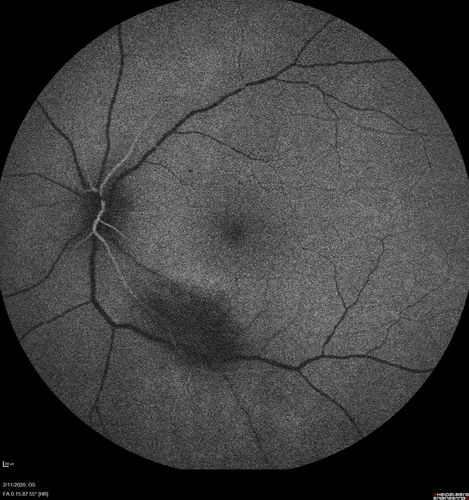

Acquired Toxoplasmosis Retinitis Para Foveal - Following Venison Consumption

56 year old man who became very sick after eating venison at the end of December 2019.  Presented 6 weeks later with a scotoma.  Initial photos show presentation with 20/63 vision.  Vision dropped to 5/200.  All tests (including PCR of anterior chamber tap) were negative except serum toxoplasmosis IgG and IgM.  Vision improved to 20/32 but the scotoma remained on oral trimetheprim/sulfa